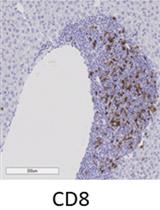

B6/lpr小鼠肝脏、肺、胰腺和结肠中免疫细胞和与体内施用的抗体结合的细胞的免疫组织化学

Immunohistochemistry of Immune Cells and Cells Bound to in vivo Administered Antibodies in Liver, Lung, Pancreas, and Colon of B6/lpr Mice

KA Kieran Adam

AM Adam Mor

3742 Views

Jul 20, 2022

Employing a novel mouse model of immune related adverse events (irAEs) induced by combination of anti-PD1 and anti-CTLA-4 antibodies, we visualized immune infiltration into the liver, lung, pancreas, and colon. Here, we describe the avidin-biotin conjugate (ABC) method used to stain T cells (CD4 and CD8), B cells (CD19), macrophages (F4/80), and cells bound by the in vivo administered rat anti-mouse antibodies for chromogenic immunohistochemistry (IHC). Using a biotinylated goat anti-rat antibody, we detected the localization of cells bound to the in vivo antibodies for PD-1 and CTLA-4. IHC has advantages over other techniques, namely antibody availability, resistance to photobleaching, and greater sensitivity. Additionally, detection and localization of in vivo antibodies can be used in mice models to infer their therapeutic efficacy, stability, and function.Graphical abstract: